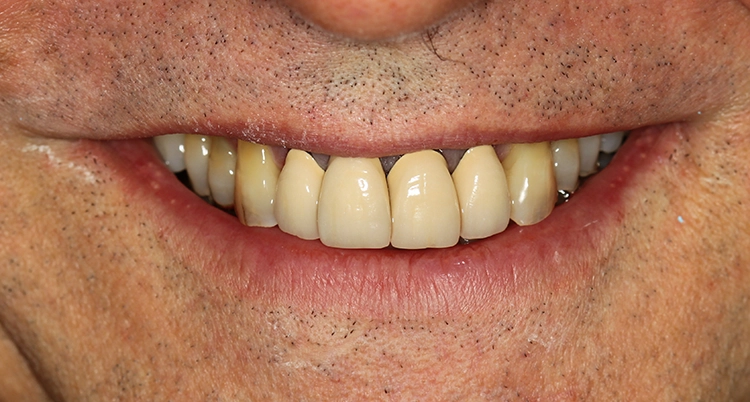

Egger/Wermuth/GrevenWeiße Ästhetik: Die Oberkieferfront empfindet der Patient als ausreichend lang. Das entspannte Lächeln zeigt 1/3 der Frontzahnlänge. Der Schneidekantenverlauf folgt der Konkavität der Unterlippe (berührungsaktives Verhältnis). Die oval imponierende Zahnform der Oberkieferfrontzähne erachtete der Patienten als harmonisch. Sie soll bei der Neuversorgung beibehalten werden (Abb. 3). Im Oberkiefer erscheint der Zahnbogen parabolisch mit Versatz im Bereich 11/21. Die Oberkieferfront steht labial (Klasse II/1).

Parodontale Gesundheit bei Attachmentverlust, Bruxismus, Erosion. Abbildung 1 sowie 6 bis 9 zeigen den Anfangsbefund als intraoralen Fotostatus.*